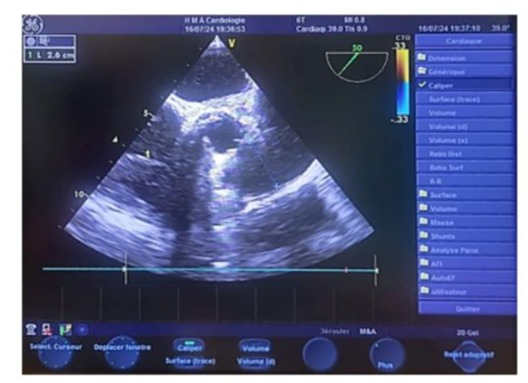

Left ventricular filling pressures were normal, and the inferior vena cava was dilated to 16 mm and slightly compliant. (Figure 3,4) The left atrium was dilated, with a surface area of 21.5 cm² and a volume of 44 ml/m². (Figure 5) The right ventricle had preserved systolic function with a TAPSE (Tricuspid Annular Plane Systolic Excursion) of 22 mm and a tissue Doppler S’ velocity of 12 cm/s. The right atrium was dilated at 19.7 cm², free of echoes. Assessment of the valvular apparatus showed a tricuspid aortic valve with degenerative changes, including calcified masses between the right and left cusps, limiting valve opening. Severe stenosis was noted, with a valvular area of 0.8 cm² (indexed area of 0.58 cm²), a Vmax of 3.93 m/s, and a mean gradient of 35 mmHg. The aortic annulus measured 19 mm, and minimal regurgitation was observed. (Figure 6-9)

Figure 6: Parasternal short-axis echographic image showing a valvular area of 0.9 cm² by planimetry (indexed area of 0.7 cm²/m²).